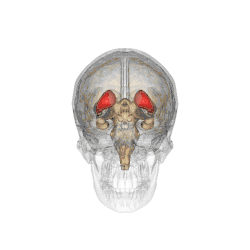

Caudate nucleus within the skull